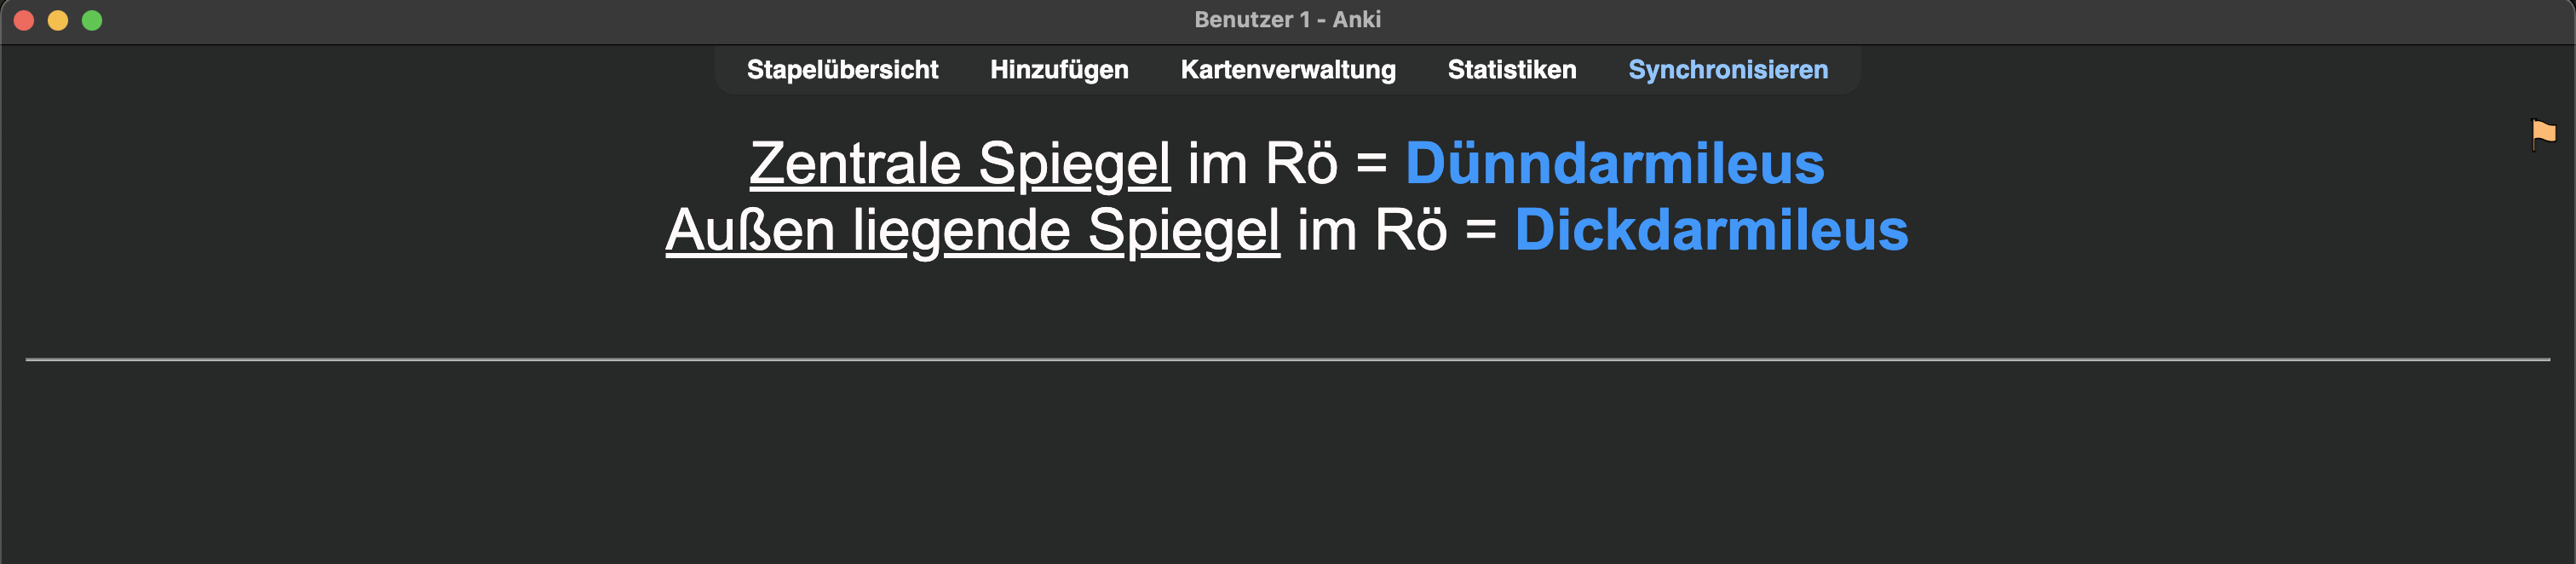

Ich konnte mir diese medizinische Information nur sehr schlecht merken:

Nach initialen erfolgreichen Wiederholungen (immer mit „Gut“ beantwortet) im weiteren Verlauf fünf Fehlversuche 😬. Also eine schlechte Karte! „Härter“ lernen bringt hier nichts; die Information ist einfach für mein Gehirn noch nicht appetitlich genug 🧀.

Also … Chunk🪓:

Das dann noch analog für den Dickdarmileus durchführen. Außer einer Karte werden also bis zu sechs. Erstmal mehr Zeitaufwand, aber auf lange Sicht ein Gewinn an Wissen und Zeit 🤑.